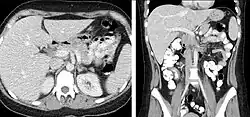

CT is an accurate technique for diagnosis of abdominal diseases like Crohn's disease,[69] GIT bleeding, and diagnosis and staging of cancer, as well as follow-up after cancer treatment to assess response.[70] It is commonly used to investigate acute abdominal pain.[71] Non-enhanced computed tomography is today the gold standard for diagnosing urinary stones.[72] The size, volume and density of stones can be estimated to help clinicians guide further treatment; size is especially important in predicting spontaneous passage of a stone.[73]